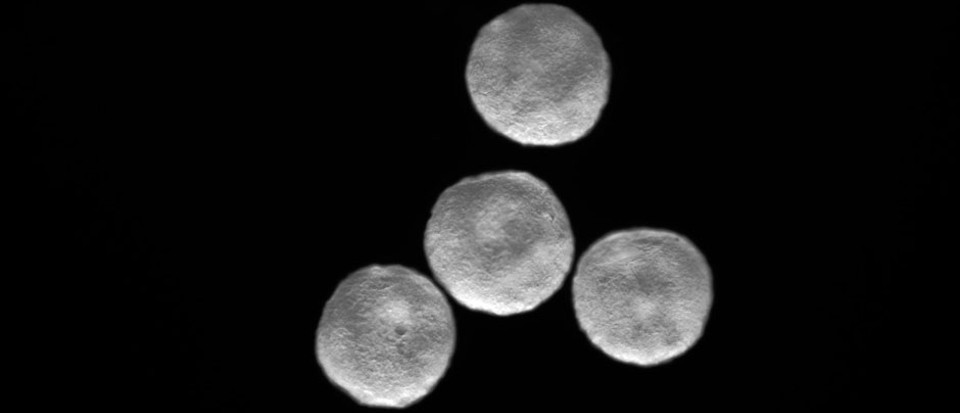

發育1周後,類器官在結構上相當於25天胚胎的心臟。在這個階段,心臟只有一個心室,這將成為成熟心臟的左心室。類器官直徑約為2毫米,包括這一發育階段常見的主要細胞類型:心肌細胞、上皮細胞、成纖維細胞和心外膜。它們也有一個清晰的心室,每分鐘跳動60到100次,這與相同年齡的胚胎心臟的速率相同

對於此次創造出的迄今為止最真實的心臟類器官,Mendjan

表示,當其第一次看到它的時候,很驚訝這些心室可以自行形成。相比其他類器官,心臟類器官的成敗顯而易見,它會跳動。迄今為止,這顆“迷你心臟”已經在實驗室中存活了3個多月,它將幫助科學家們瞭解心臟發育的前所未有的細節。